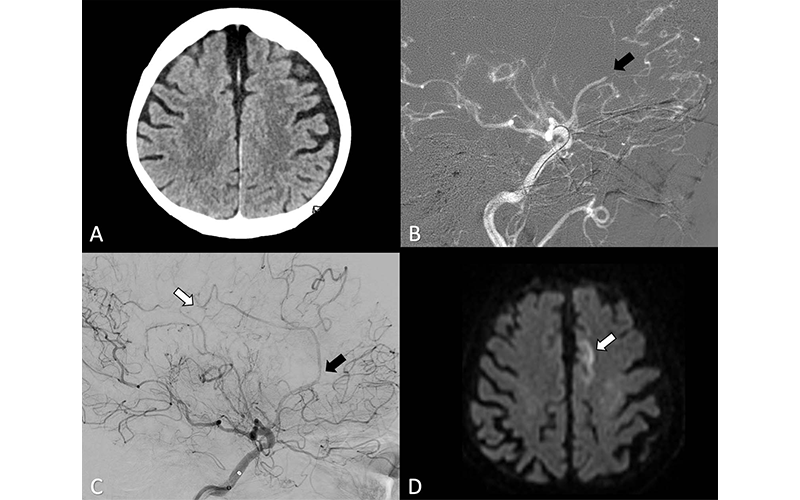

(A–C) Axial perfusion CT (time-to-maximum, >6 seconds) at admission shows a bilateral deficit (arrows in A) in the territory of the anterior cerebral artery (ACA; ie, azygos variant) because of a distal occlusion of the A3 segment (white arrow, sagittal view in B). Stent retriever thrombectomy (black arrow, sagital view in B) was performed with full reperfusion shown on the final digital subtraction angiography image (arrow, sagittal view in C). (D) Follow-up at 24 hours shows no sign of infarction in the ACA on the axial contrast-unenhanced CT image.